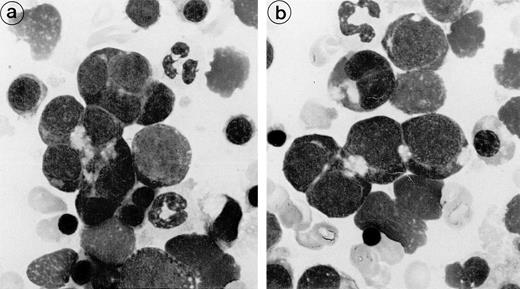

Bone marrow aspirates from the 3 patients showed marked hypercellularity and erythroid hyperplasia (>70% for case nos. 1 and 2). Bone marrow smear from patient 3 showed diffuse lymphocytic infiltration (86%) and numerous erythroid islands (Fig1). The main abnormalities observed in the bone marrow smears of the 3 patients were the presence of numerous erythroid islands, with aggregated erythroblasts and frequent binuclear forms. Most often, adjacent cells shared the appearance of the same maturation stage, but some cells of apparently different maturity were also in close contact. A nonbasophilic clear area was observed at sites of close proximity between adjacent erythroblasts. This feature allowed a distinction to be made between this type of erythroid island and that of sideroblastic anemia. No macrophages were found in contact with these erythroblast clusters.

Bone marrow smear (patient 2): The erythroblasts are numerous and several of them are closely apposed to each other. At the intercellular junction, a clear nonbasophilic zone is evident.